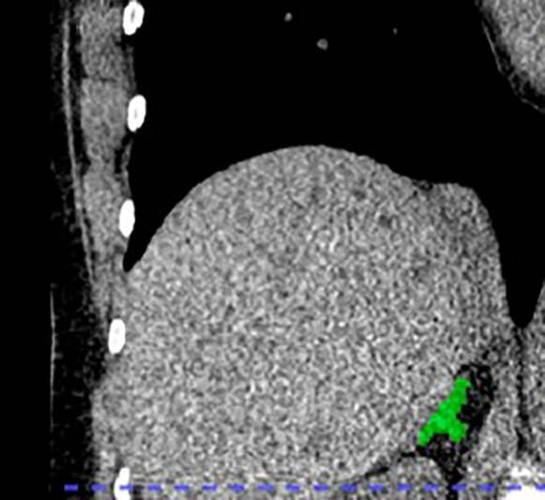

Lead author of the new study, Dr. Elena Ghotbi, developed and trained a deep learning model to measure adrenal gland volume on existing CT scans.

The team applied their deep learning model to the CT scans to segment and calculate the volume of the adrenal glands.